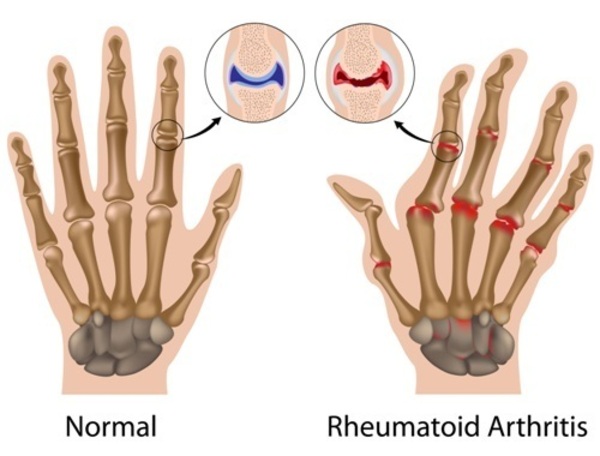

The two main types of arthritis — osteoarthritis and rheumatoid arthritis — damage joints in different ways.

Osteoarthritis

The most common type of arthritis, osteoarthritis involves wear-and-tear damage to your joint’s cartilage — the hard, slick coating on the ends of bones where they form a joint. Cartilage cushions the ends of the bones and allows nearly frictionless joint motion, but enough damage can result in bone grinding directly on bone, which causes pain and restricted movement. This wear and tear can occur over many years, or it can be hastened by a joint injury or infection.

Osteoarthritis also affects the entire joint. It causes changes in the bones and deterioration of the connective tissues that attach muscle to bone and hold the joint together. It also causes inflammation of the joint lining.

Rheumatoid Arthritis

In rheumatoid arthritis, the body’s immune system attacks the lining of the joint capsule, a tough membrane that encloses all the joint parts. This lining (synovial membrane) becomes inflamed and swollen. The disease process can eventually destroy cartilage and bone within the joint.